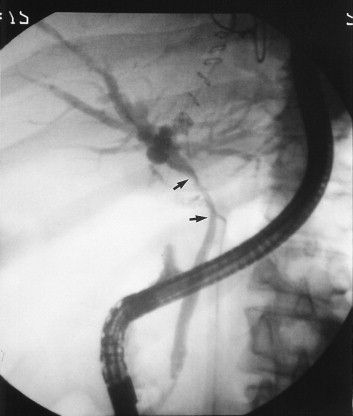

syndrome consists of a triad; cystic duct gall-stone (or gall-stone in the Hartmann's pouch), chronic cholecystitis with shrunken gall-bladder, and benign stenosis of the common hepatic of common bile duct [1]. The reported incidence of this syndrome is 1% of all cholecystectomies [